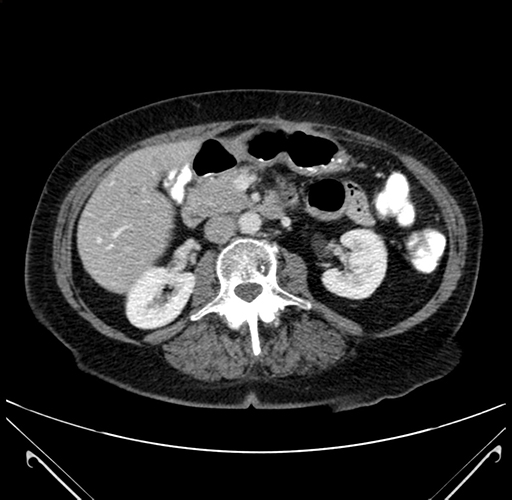

Axial Venous